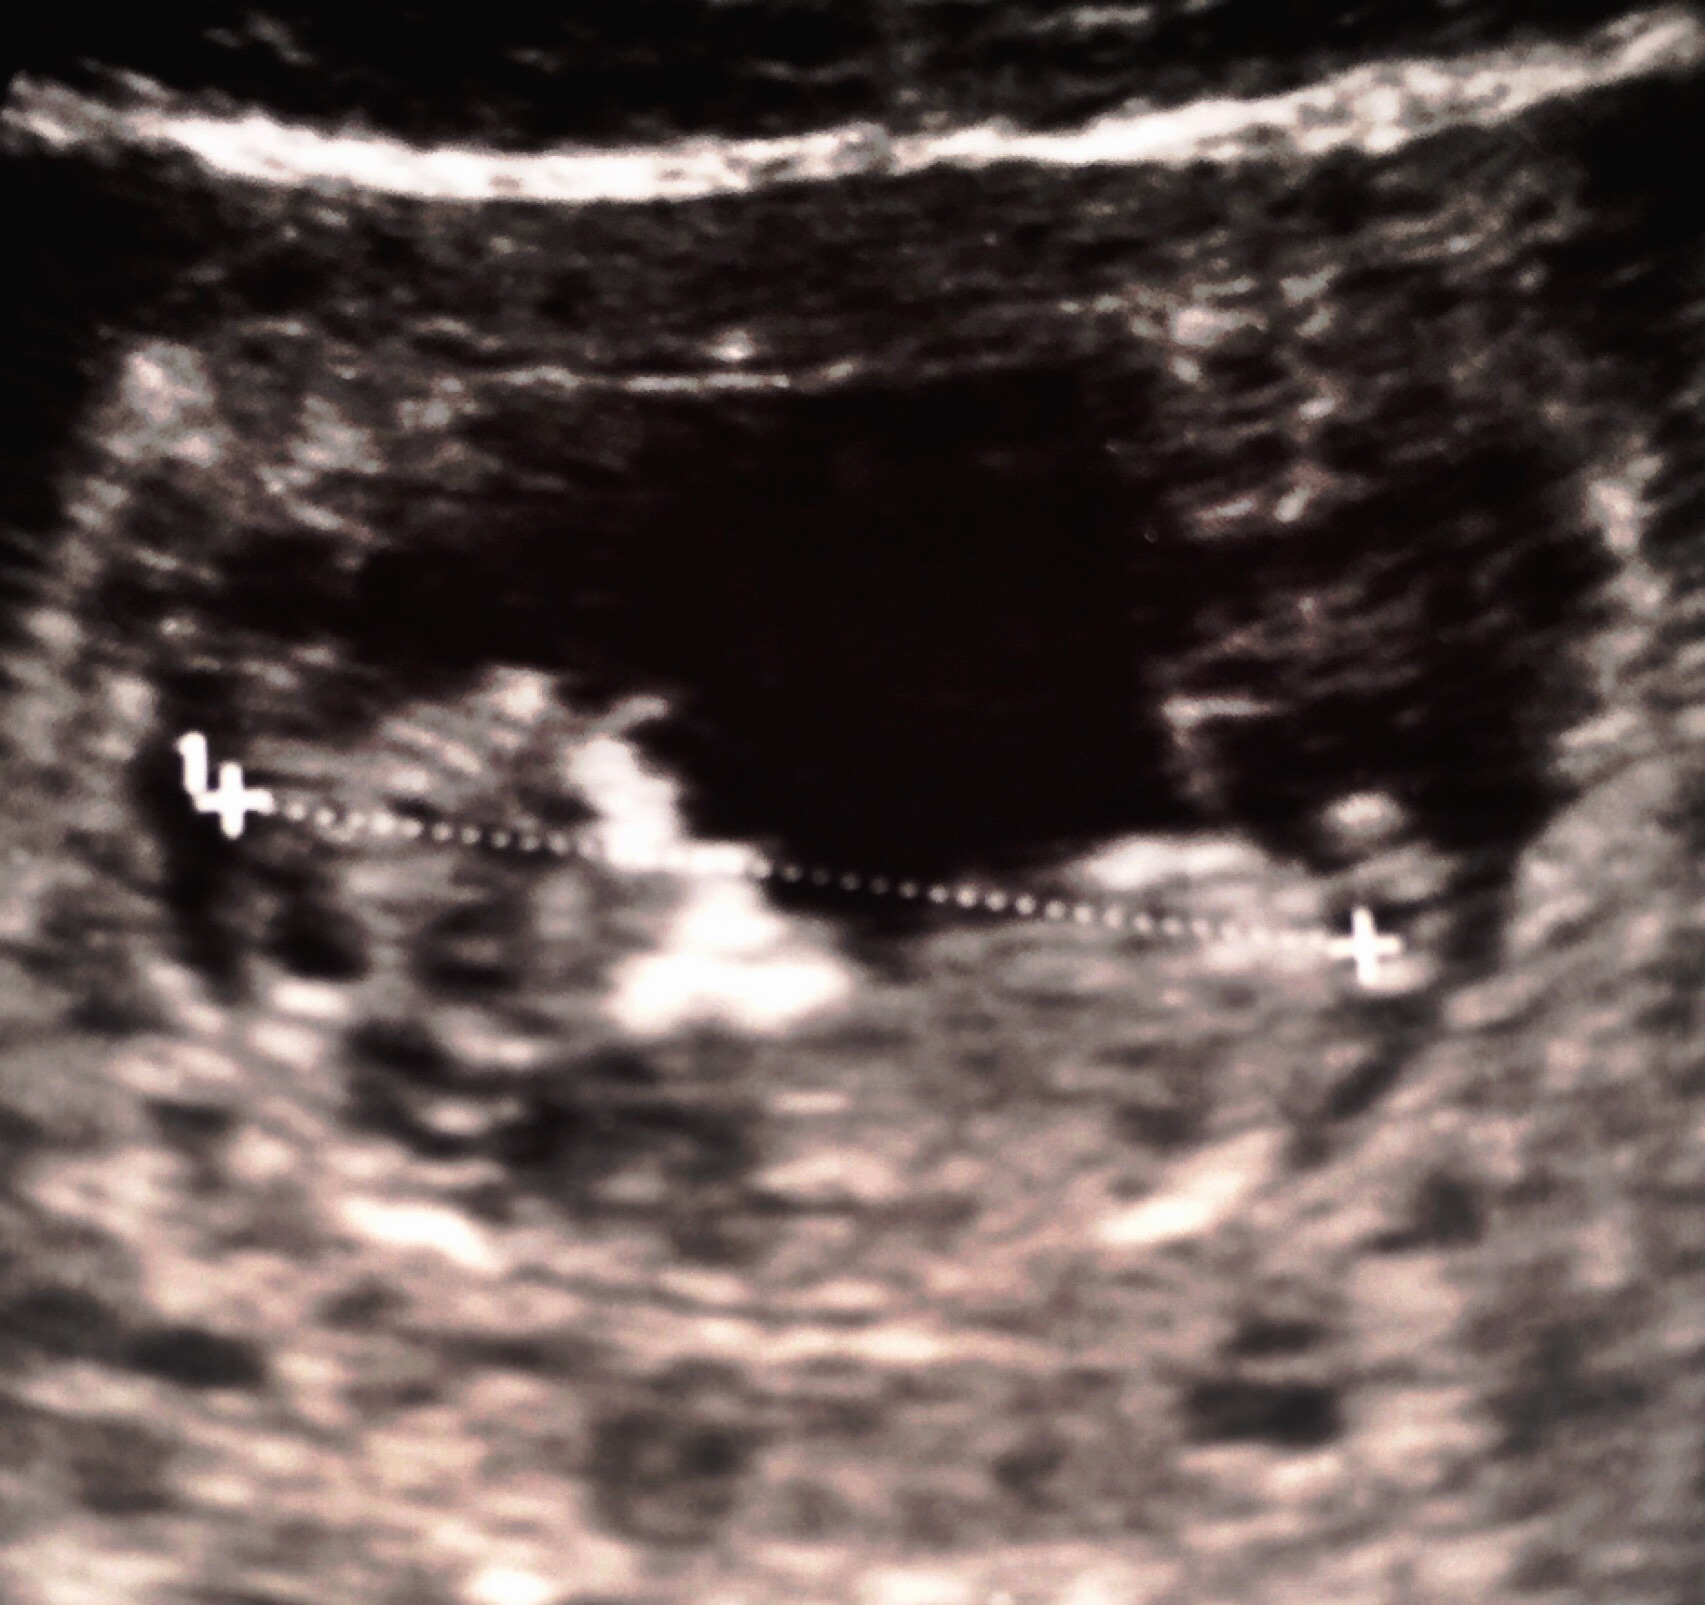

Any ideas?! :) 12w

May be too early to tell - but give it a shot! :-)

Boy?